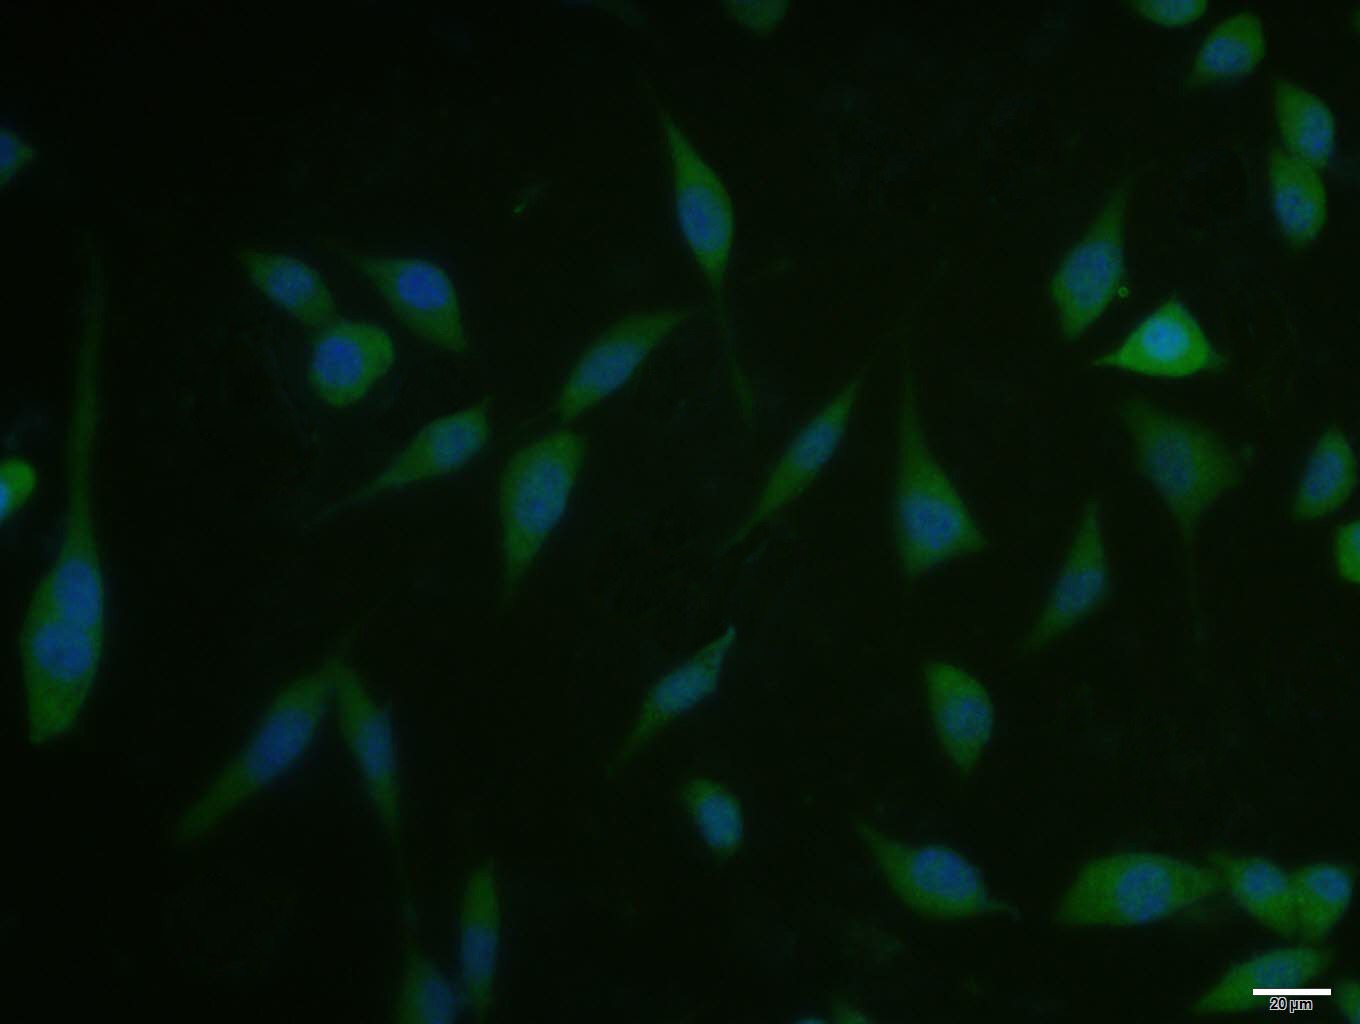

| Verified Activity | 1. Blank control: A431. Primary Antibody (green line): Rabbit Anti-Phospho-mTOR (Ser2481) antibody (TMAB-01459) Dilution: 1 μg/Test; Secondary Antibody: Goat anti-rabbit IgG-AF488 Dilution: 0.5 μg/Test. Protocol The cells were fixed with 4% PFA (10 min at room temperature) and then permeabilized with 90% ice-cold methanol for 20 min at-20°C. The cells were then incubated in 5% BSA to block non-specific protein-protein interactions for 30 min at room temperature. Cells stained with Primary Antibody for 30 min at room temperature. The secondary antibody used for 40 min at room temperature. 2. A431 cell; 4% Paraformaldehyde-fixed; Triton X-100 at room temperature for 20 min; Blocking buffer (normal goat serum) at 37°C for 20 min; Antibody incubation with (Phospho-mTOR (Ser2481)) polyclonal Antibody, Unconjugated (TMAB-01459) 1:100, 90 minutes at 37°C; followed by a conjugated Goat Anti-Rabbit IgG antibody at 37°C for 90 minutes, DAPI (blue) was used to stain the cell nucleus. 3. Sample: Hepg2 (Human) Cell Lysate at 30 μg Primary: Anti-Phospho-mTOR (Ser2481) (TMAB-01459) at 1/300 dilution Secondary: IRDye800CW Goat Anti-Rabbit IgG at 1/20000 dilution Predicted band size: 289 kDa Observed band size: 289 kDa 4. Tissue/cell: rat brain tissue; 4% Paraformaldehyde-fixed and paraffin-embedded; Antigen retrieval: citrate buffer (0.01M, pH6.0), Boiling bathing for 15 min; Block endogenous peroxidase by 3% Hydrogen peroxide for 30 min; Blocking buffer (normal goat serum) at 37°C for 20 min; Incubation: Anti-Phospho-mTOR (Ser2481) Polyclonal Antibody, Unconjugated (TMAB-01459) 1:200, overnight at 4°C, followed by conjugation to the secondary antibody and DAb staining. 5. Paraformaldehyde-fixed, paraffin embedded (mouse brain tissue); Antigen retrieval by boiling in sodium citrate buffer (pH6.0) for 15 min; Block endogenous peroxidase by 3% hydrogen peroxide for 20 min; Blocking buffer (normal goat serum) at 37°C for 30 min; Antibody incubation with (Phospho-mTOR (Ser2481)) Polyclonal Antibody, Unconjugated (TMAB-01459) at 1:200 overnight at 4°C, followed by operating according to SP Kit (Rabbit) instructionsand DAB staining. 6. Blank control: mouse splenocytes (blue) Isotype Control Antibody: Rabbit Igg (orange); Secondary Antibody: Goat anti-rabbit IgG-FITC (white blue), Dilution: 1:100 in 1 X PBS containing 0.5% BSA; Primary Antibody Dilution: 5 μL in 100 μL 1X PBS containing 0.5% BSA (green). 7. Blank control (blue line): Hela (fixed with 70% ethanol (Overnight at 4°C) and then permeabilized with 90% ice-cold methanol for 30 min on ice) Primary Antibody (green line): Rabbit Anti-Phospho-mTOR (Ser2481) antibody (TMAB-01459), Dilution: 1 μg/10^6 cells; Isotype Control Antibody (orange line): Rabbit IgG. Secondary Antibody (white blue line): Goat anti-rabbit IgG-FITC, Dilution: 1 μg/test. 8. Paraformaldehyde-fixed, paraffin embedded (rat brain); Antigen retrieval by boiling in sodium citrate buffer (pH6.0) for 15 min; Block endogenous peroxidase by 3% hydrogen peroxide for 20 min; Blocking buffer (normal goat serum) at 37°C for 30 min; Antibody incubation with (Phospho-mTOR (Ser2481)) Polyclonal Antibody, Unconjugated (TMAB-01459) at 1:200 overnight at 4°C, followed by operating according to SP Kit (Rabbit) instructionsand DAB staining. 9. Sample: Jurkat (Human) Cell Lysate at 30 μg MCF-7 (Human) Cell Lysate at 30 μg Primary: Anti-Phospho-mTOR (Ser2481) (TMAB-01459) at 1/1000 dilution Secondary: IRDye800CW Goat Anti-Rabbit IgG at 1/20000 dilution Predicted band size: 289 kDa Observed band size: 289 kDa ![]() ![]() ![]() ![]() ![]() ![]() ![]() ![]() ![]() |